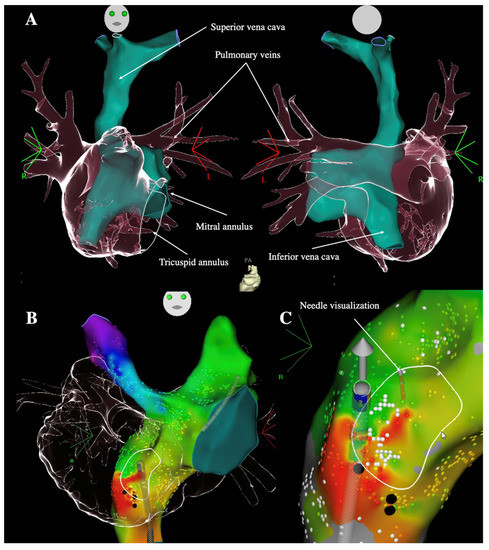

- Guarguagli, S.; Cazzoli, I.; Kempny, A.; Gatzoulis, M.A.; Ernst, S. Initial Experience Using the Radiofrequency Needle Visualization on the Electroanatomical Mapping System for Transseptal Puncture. Cardiol. Res. Pract. 2020, 2020, 5420909. [Google Scholar] [CrossRef]